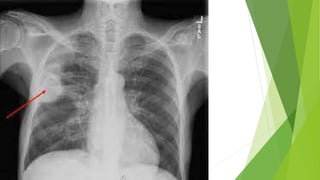

 Radiological : Chest x-ray and CT scan of chest

Investigation  Radiological :Chest x-ray and CT scan of chest  Sputum examination: AFB stain At least two sputum samples (including at least one obtained in the early morning)  Sputum Culture  Pleural fluid Examination: ADA(adenosine Deaminase)  Xpert MTB/Rif (Nucleic acid amplification test NAAT)  Bronchoscopy  Tuberculin skin test :  Baseline Blood tests: CBC, CRP, ESR, Urea, and electrolytes, LFT